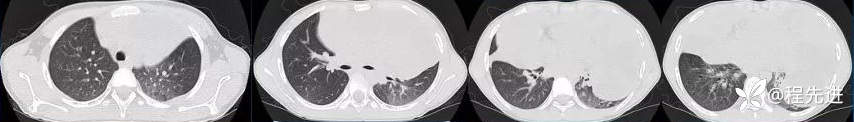

CT

平扫

肺窗